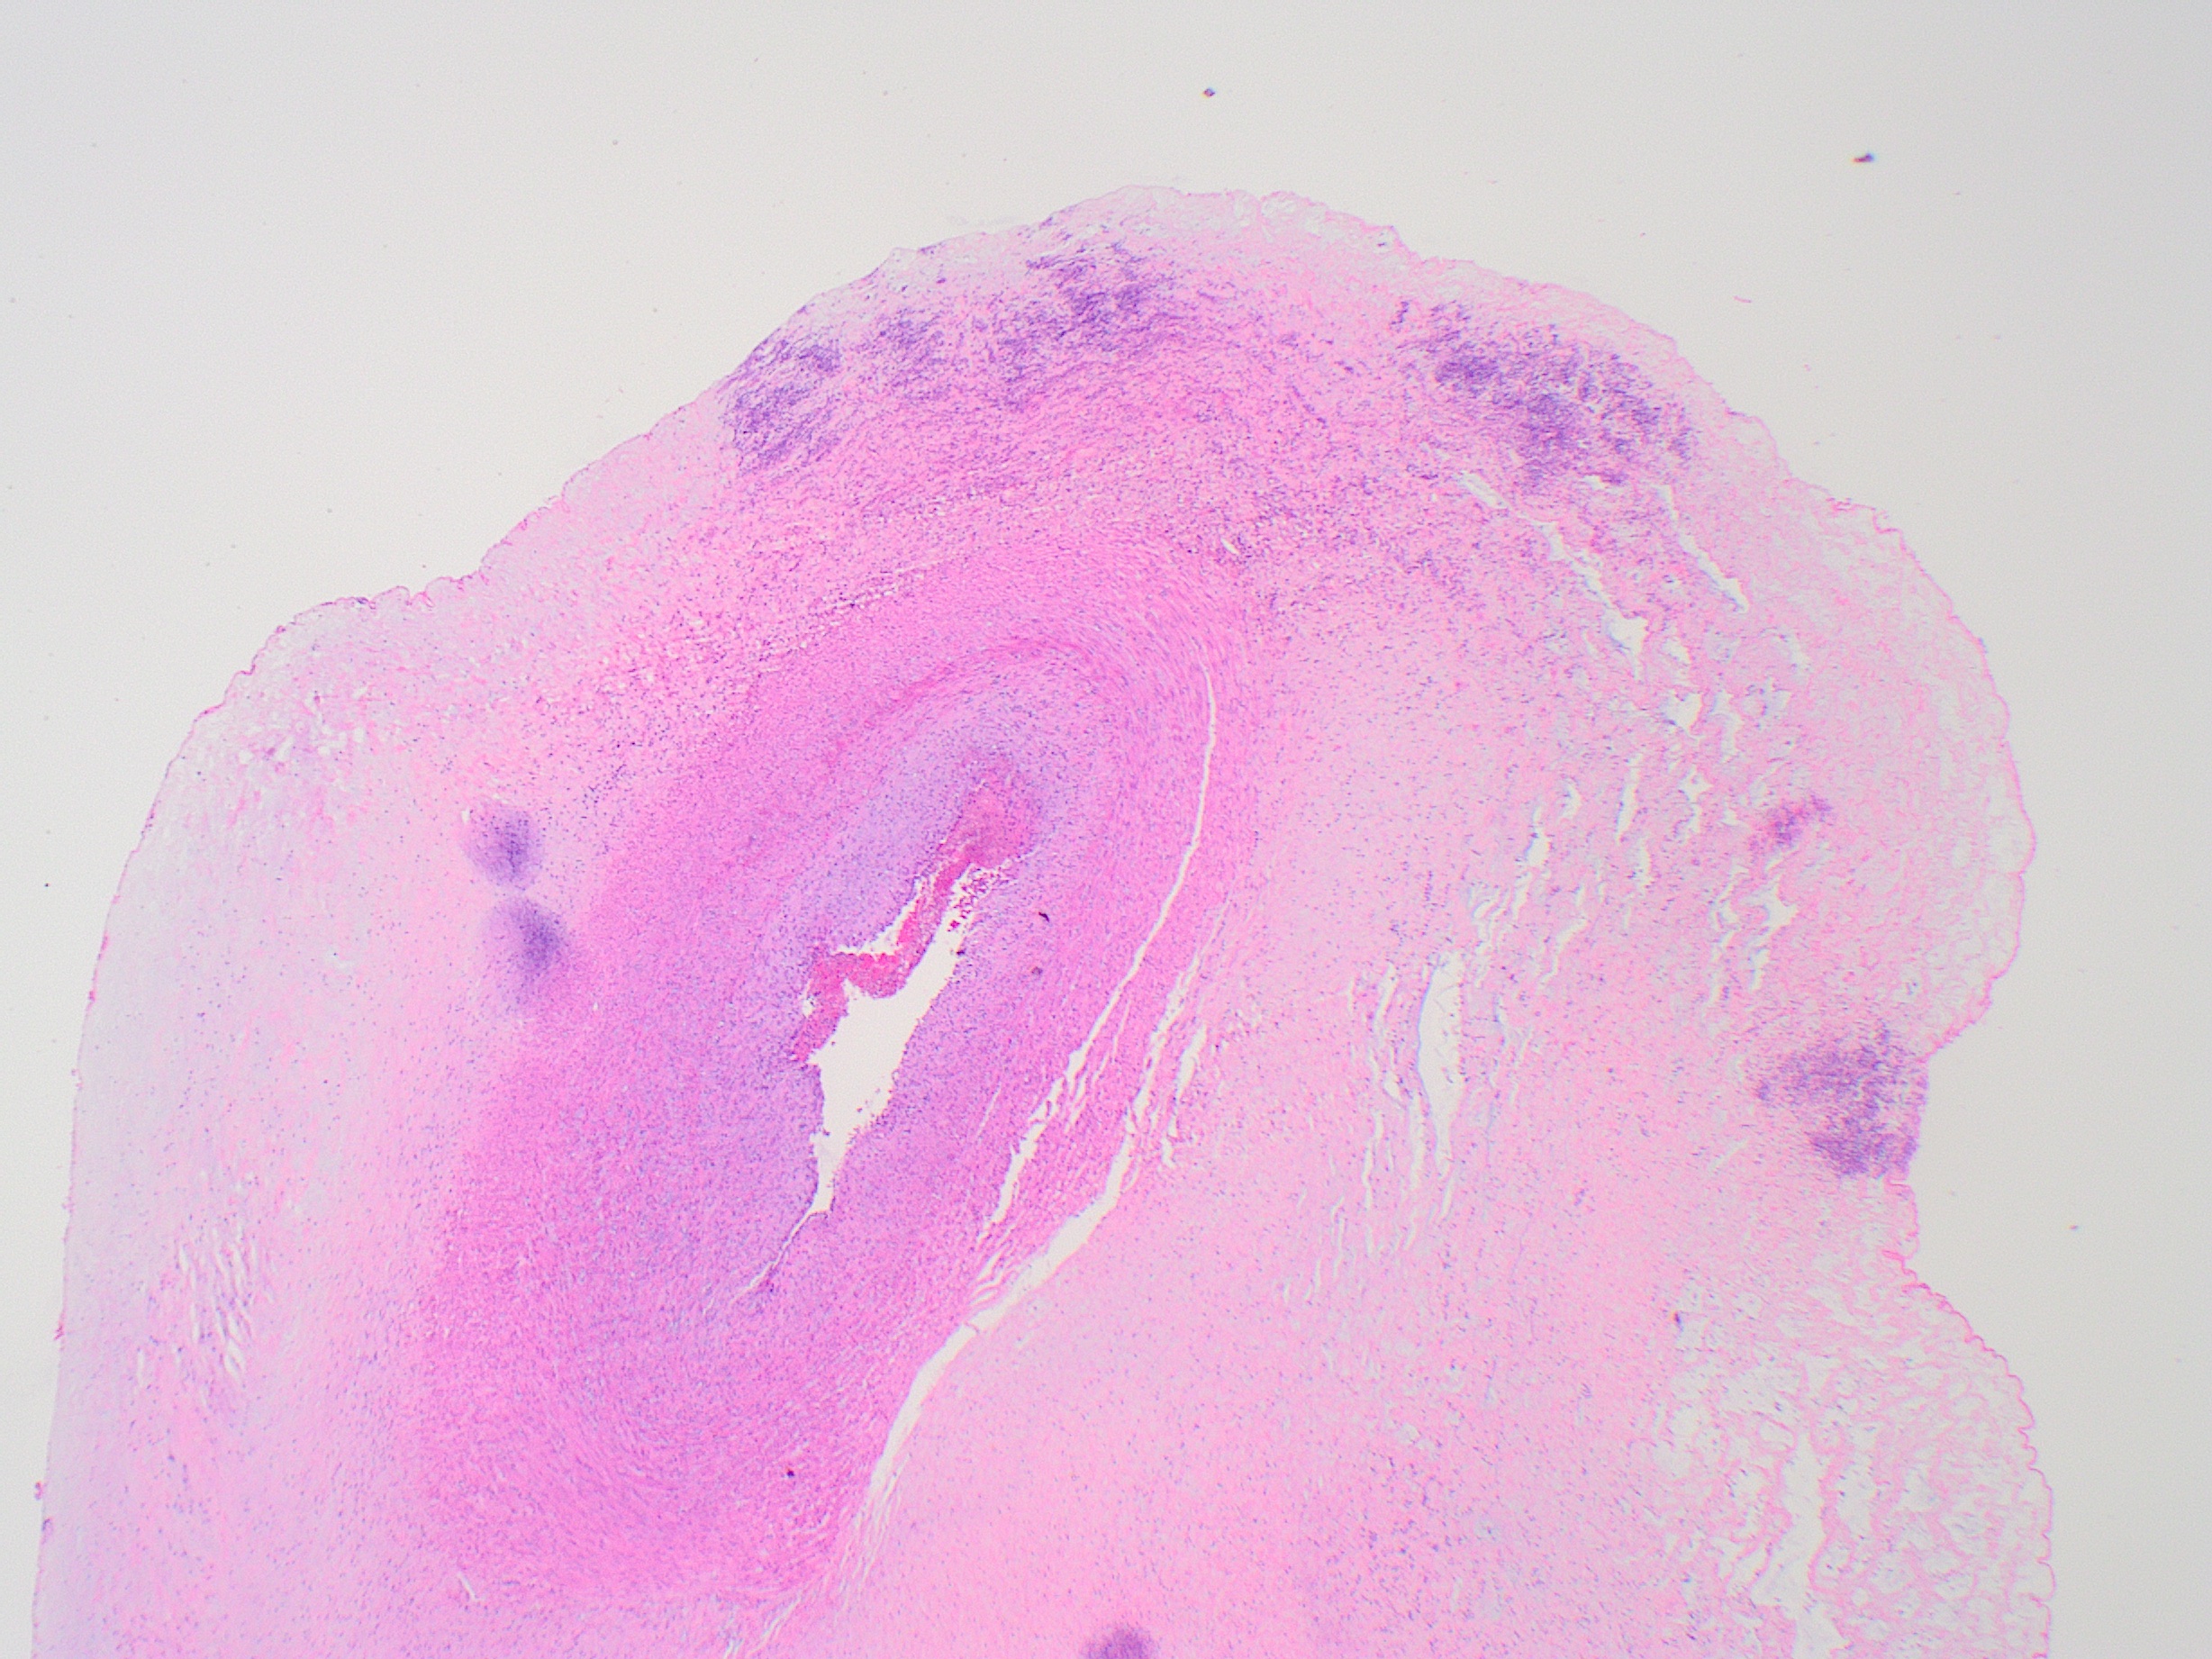

Placenta, 27 weeks gestation.

The photographs depict multifocal subamniotic microabscesses of the umbilical cord, most likely due to fungal infection of the placenta. Ascending infection of the amniotic fluid is the most likely route of infection. The most common etiologic organism in fungal infection of the amniotic fluid is Candida species; speciation is not possible based on morphologic features.

The most characteristic finding of fungal infection in the placenta is multifocal peripheral microabscesses involving the umbilical cord. Grossly, these appear as yellow-white, punctate lesions as pictured. Microscopically, the lesions show well-formed subamniotic foci of leukocytoclastic necrosis. Organisms are not usually visible on H&E stains, but pseudohyphae are readily demonstrated within some of the lesions on GMS stain. PAS will also highlight pseudohyphae, but will have higher background artifact. Particularly in well-developed microabscesses with dense inflammation, pseudohyphae may not be visible in all lesions and multiple sections may be needed to demonstrate the fungus. Acute chorioamnionitis is also a consistent feature of intrauterine fungal infection (not pictured).